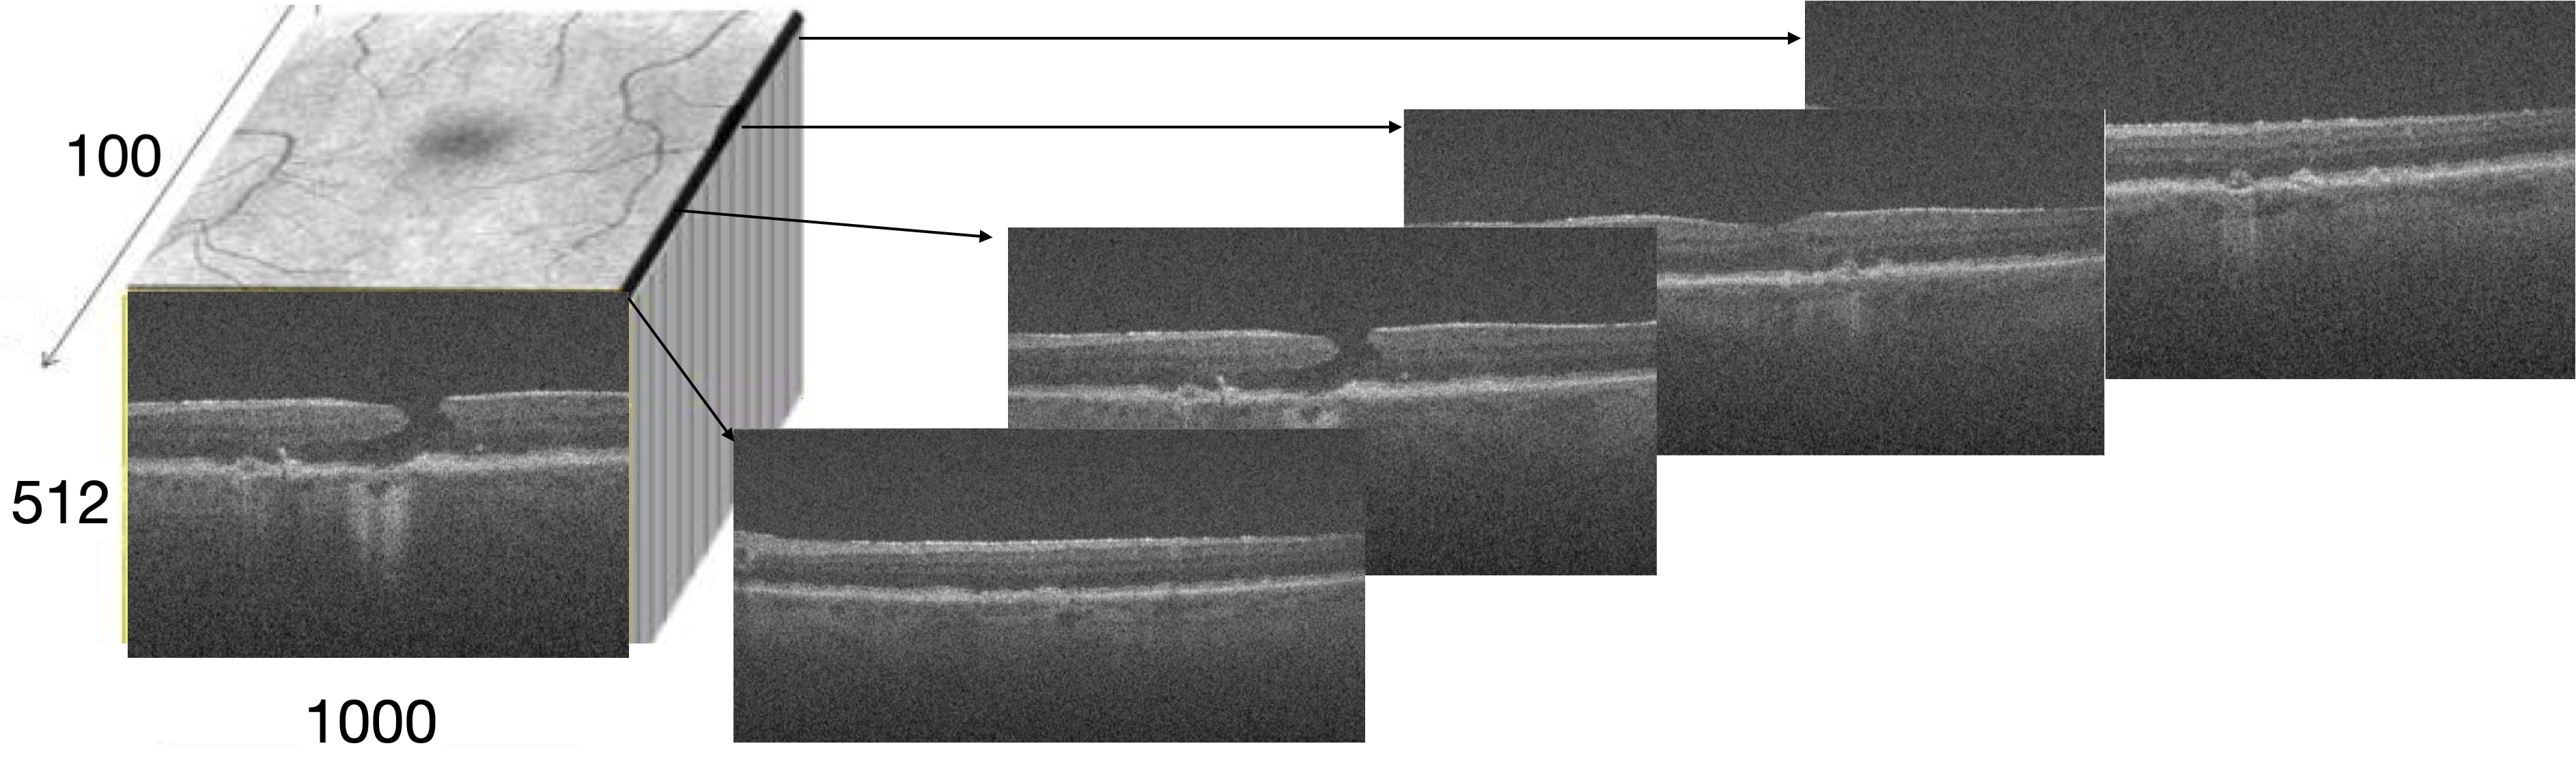

GA dataset descriptions Our GA dataset is derived from the A2A SD-OCT Study (http://ClinicalTrials.gov identifier NCT00734487), which was an ancillary observational prospective study of a subset of eyes from the AREDS2 conducted at four sites (National Eye Institute, Duke Eye Center, Emory Eye Center, and Devers Eye Institute) [34]. In this experiment (with our new dataset, that we will make public), each OCT volume image consists of 100100100 scans, each of which being a 512×10005121000512\times 1000 pixel image [5]. 1,08510851,085 OCT images are collected from 275275275 subjects during 555 years. An example of 3D OCT images is shown in Figure. 10.

Refer to caption

Figure 10: Illustration of a 3D OCT image example.